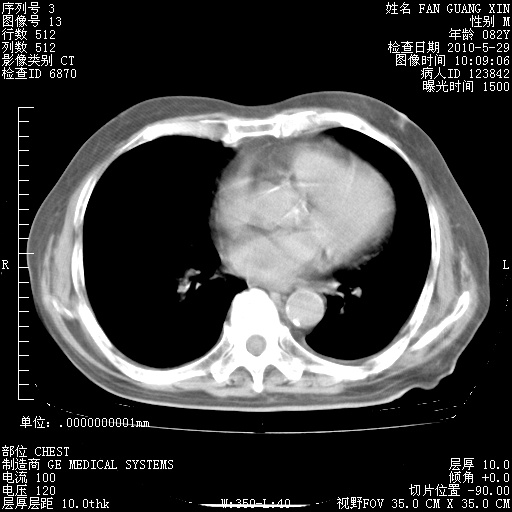

治疗3周后的肺部CT纵隔窗

再治疗10天后的肺部CT

再治疗10天后的肺部CT 纵膈窗

阅读此次胸部CT,肺间质渗出性改变较入院时有吸收。目前从体温、白细胞、中性分叶明显增高,肯定存在细菌感染(发生医院感染哦,若无消化道及泌尿系统等感染的依据,肺部感染可能大)。若你院头孢哌酮舒巴坦钠耐药率较高,同意你的方案,若48小时体温仍高,可考虑使用碳青霉稀类抗菌药物,同时可予超声雾化、注意滴数时加大液体量。白蛋白33.30g/L较低哦,需加强营养等支持治疗。